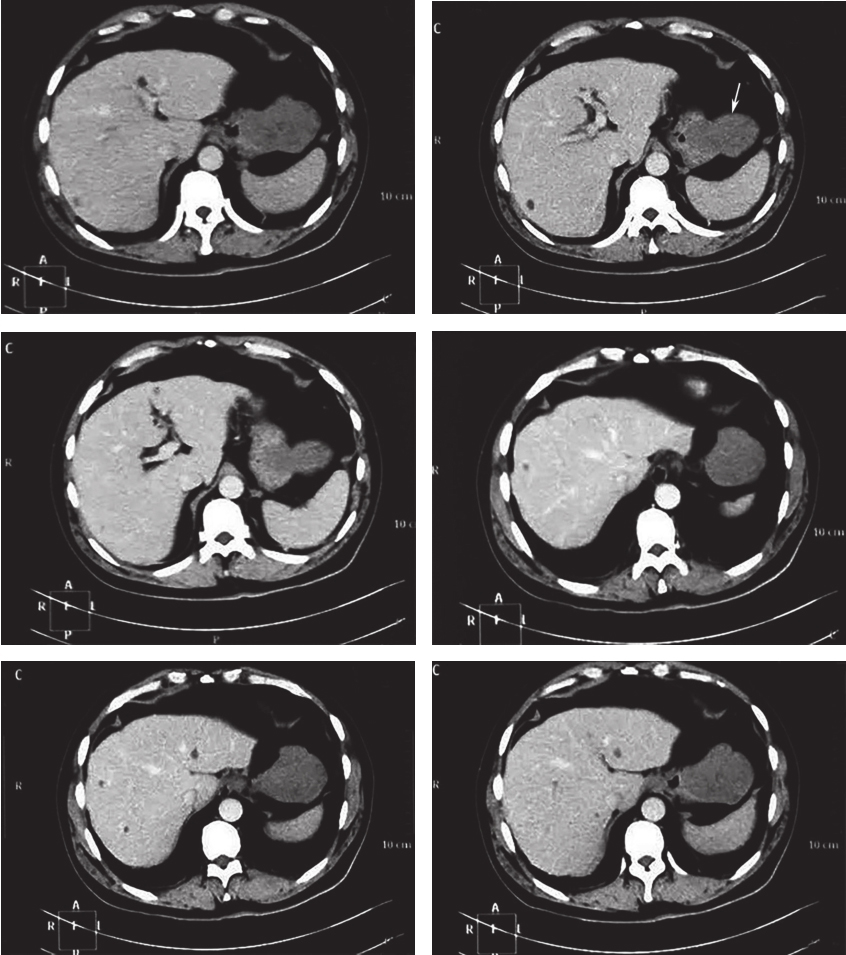

腹部增强CT:胃底部占位灶,考虑GIST?肝内多发囊肿,胆囊多发结石,双肾多发囊肿(图1)。

图1 CT提示胃底部占位灶